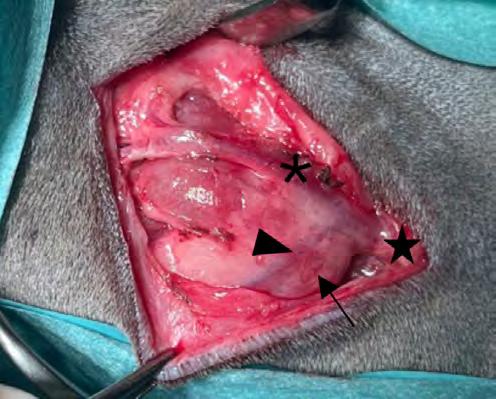

minal generalizada y una masa hipoecoica de 2,6 cm de diámetro en la zona de proyección de los linfonodos mesentéricos (Fig. 1). También se observaron hallazgos ecográficos compatibles con peritonitis, como aumento de la ecogenicidad difusa del peritoneo y presencia de líquido libre anecoico, en este caso no puncionable. Por cuestiones económicas los tutores rechazaron ampliar los análisis sanguíneos con un proteinograma. Se hospitalizó el paciente con un tratamiento inicial de amoxicilina-clavulánico (22 mg/kg/12 h/IV Amoxicilina/Ácido clavulánico Normon 1000 mg/200 mg inyectable, Normon, Madrid, España), maropitant (1 mg/kg/24 h/IV, Prevomax Dechra, Uldum, Dinamarca) y fluidoterapia (Lactato de Ringer). Para el tratamiento del dolor se le administró en infusión con-

Bajo sedación con butorfanol (0,1 mg/kg IV Torphasol, aniMedica Senden-Bösensell, Alemania) y alfaxolona (5 mg/kg IV, Alfaxan Dechra, Uldum, Dinamarca) se le realizó una punción con aguja fina ecoguiada de bazo y linfonodo mesentérico caudal. La citología fue compatible con inflamación piogranulomatosa, sin observarse una causa subyacente.

los linfonodos mesentérico caudal, sublumbar e ilíacos pálidos y de aspecto granuloso. Se tomaron muestras de estos linfonodos para histopatología y cultivo. Se realizaron lavados y aspiración de la cavidad abdominal con solución salina y se cerró por planos de forma rutinaria. El paciente se recuperó de manera satisfactoria.

El estudio histopatológico mostró una linfadenitis piogranulomatosa grave y generalizada; la totalidad de los fragmentos evaluados estaban ocupados por múltiples piogranulomas compuestos por centros de tejido necrótico y neutrófilos degenerados rodeados por abundantes macrófagos, células linfoplasmocitarias y fibroblastos reactivos. No se visualizaron microorganismos. La muestra fue positiva al RT-PCR (Real Time Polymerase Chain Reaction) del coronavirus entérico del hurón (FECV). El cultivo microbiológico resultó negativo. El diagnóstico de enfermedad por coronavirus sistémico del hurón (FSCVD) se confirmó mediante el análisis inmunohistoquímico frente al coronavirus felino del linfonodo mesentérico remitido. El anticuerpo utilizado presentaba positividad cruzada con el FSCV (Idexx laboratorios, Barcelona, España) (Fig. 2).

mesentérico 60 x. Tinción inmunohistoquímica. Numerosos macrófagos presentan inmunopositividad frente al anticuerpo con positividad cruzada con el coronavirus sistémico del hurón. Imagen cortesía de Laboratorios IDEXX.

Figura 1. Imagen ecográfica longitudinal del abdomen caudal. Masa heterogénea, principalmente hipoecoica, de 2,6 cm de diámetro, con hiperecogenicidad de la grasa adyacente.

Figura 2. Imagen histológica

linfonodo